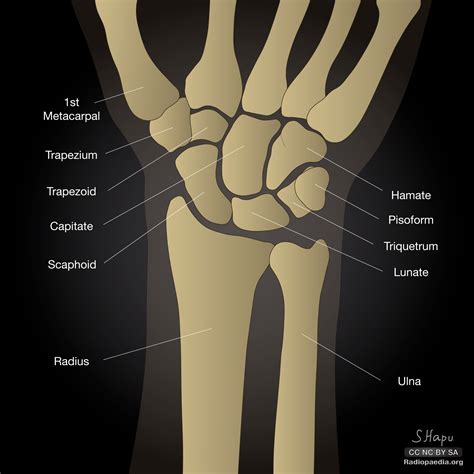

Anatomy of the Wrist

The wrist is a complex structure composed of multiple bones, ligaments, and tendons. It connects the hand to the forearm and allows for a wide range of movements. The primary bones in the wrist include:

• Carpal Bones: There are eight carpal bones in the wrist, arranged in two rows. These bones are small and irregularly shaped, providing stability and flexibility to the wrist.

• Metacarpal Bones: These five bones connect the carpal bones to the phalanges (finger bones).

• Radius and Ulna: These are the two bones of the forearm that articulate with the carpal bones to form the wrist joint.